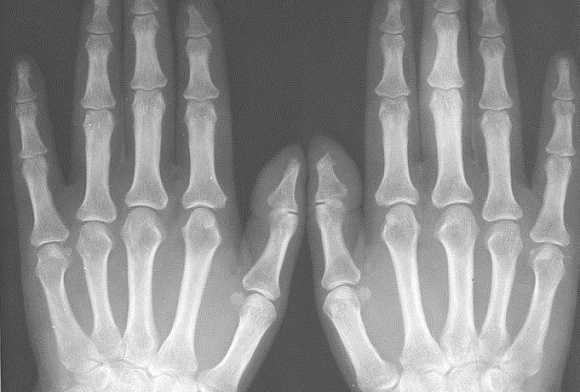

Также хотелось обратить внимание на неправильно выбираемую зону обследования. Например, зачастую при наличии односторонних клинических изменений в одном пястно-фаланговом или плюсне-фаланговом суставе врачи ограничиваются рентгенографией исключительно этой области. Однако, именно характер патологических изменений в обеих кистях, их локализация и распространённость, анализ того какие группы суставов изменяются в самом начале заболевания должны обязательно учитываться при оценке рентгенограмм для того, чтобы правильно интерпретировать полученные данные и провести дифференциальный диагноз между различными ревматическими заболеваниями. Поэтому в ревматологической практике для уточнения диагноза необходимо проводить по показаниям либо прямую сравнительную рентгенограмму кистей с захватом лучезапястных суставов либо прямую сравнительную рентгенограмму стоп.

Исходя из нашего опыта, результаты рентгенографии нередко могут зависеть от техники и правильного позиционирования объекта съемки. В настоящее время требованием всех протоколов исследований является соблюдение максимально унифицированных условий проведения рентгенограмм кистей и стоп. Так для общей оценки поражения суставов необходимо снимать обе кисти или стопы на одной пленке, обязателен захват лучезапястного сустава. Требования к расположению пациента при рентгенографии кистей и стоп изложены в соответствующих руководствах по рентгенологии. Врачу общей практики при направлении к рентгенологу обязательно необходимо указывать, что больной направляется на сравнительную рентгенограмму кистей в прямой проекции с захватом лучезапястных суставов или на прямую сравнительную рентгенограмму стоп.